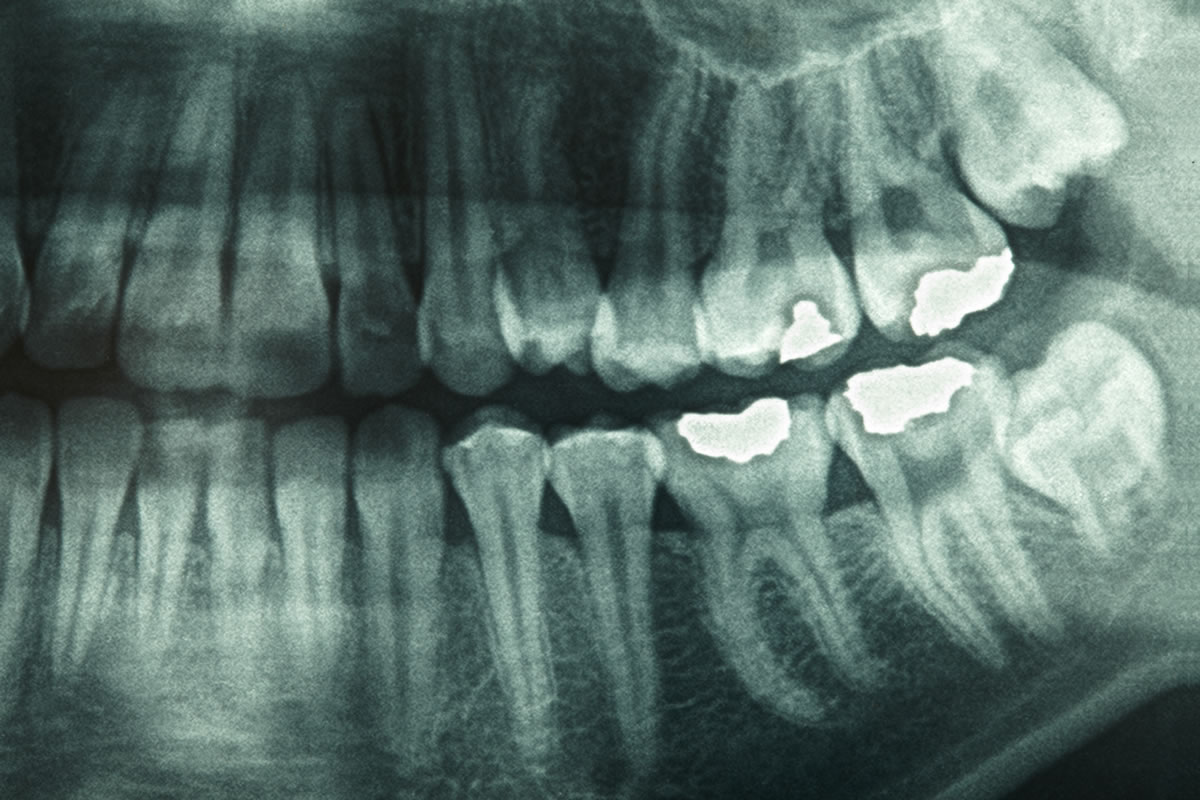

Dental X-Ray

Dental X-rays are a useful diagnostic tool when helping your dentist detect damage and disease not visible during a regular dental exam.

Dental X-rays can spot trouble early on in your mouth, teeth, gums and jaw. Treating problems before they get serious can save money, pain and sometimes even your life. At Clinic In House "Advanced Digital OPG (Full mouth X-Ray) facility available.

What types of problems do X-rays help detect?

X-rays help your dentist diagnose problems in your teeth and jaws. In adults, X-rays show:

Decay, especially small areas of decay between teeth.

Changes in the bone or root canal due to infection.

Cysts and some types of tumors

Bone loss in the jaw